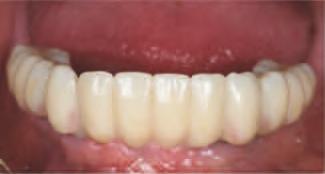

15. Vedere extraorală a restaurărilor finale livrate.

16. Vedere intraorală a restaurărilor finale mandibulare livrate.

În cab net, restaurăr le prov zor au fost deșurubate ș îndepărtate d n cav tatea orală pentru ca restaurăr le f nale să poată f l vrate ș strânse cu un cuplu de 15 Ncm, conform recomandăr producătorulu (f g. 15,16). Ajustăr le ocluzale f nale au fost m n me ș efectuate ntraoral pr ntr-o ultmă lustru re a zonelor ajustate.